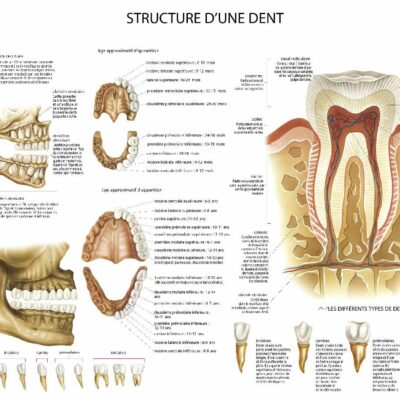

Tableaux murale pour la décoration intérieure d’un cabinet médical dentiste